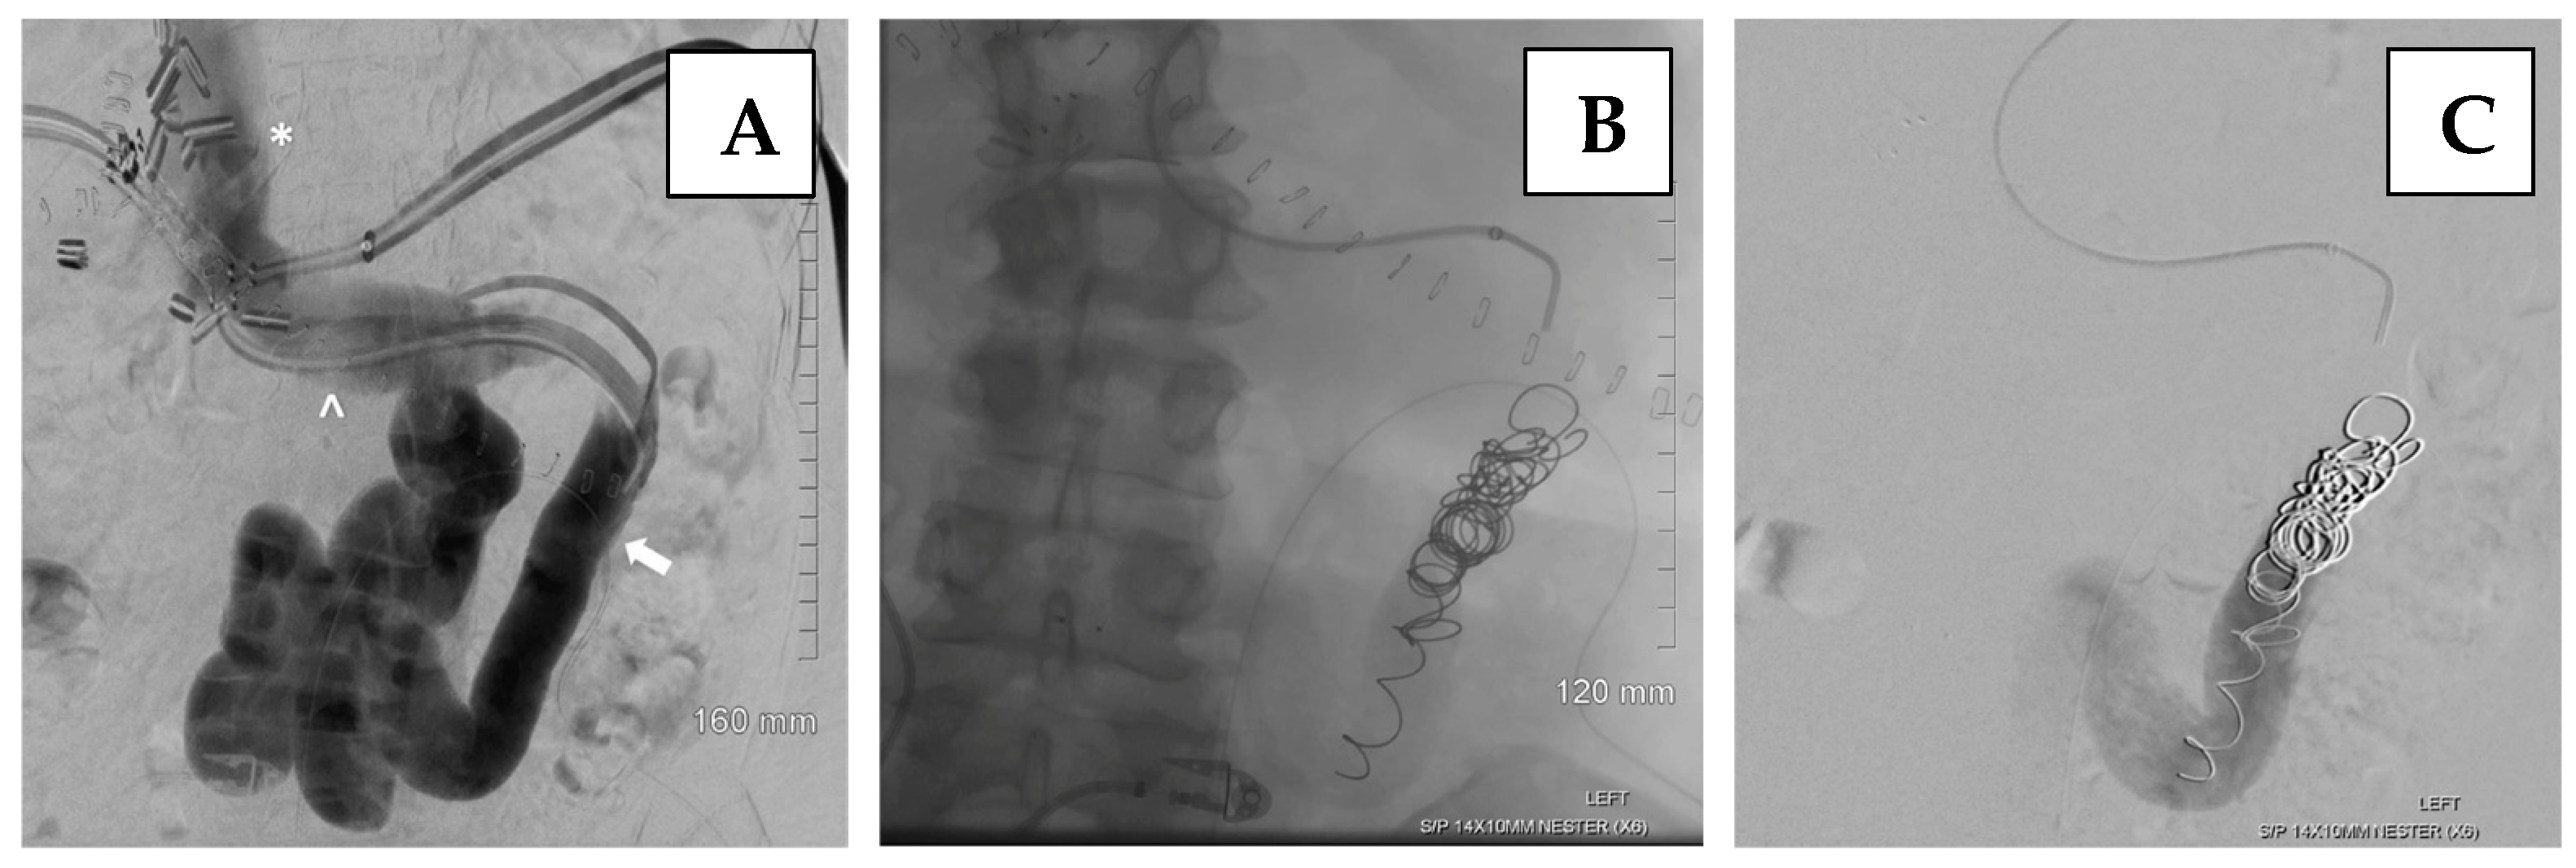

- Nicolau-Raducu, R.; Livingstone, J.; Salsamendi, J.; Beduschi, T.; Vianna, R.; Tekin, A.; Selvaggi, G.; Raveh, Y. Visceral arterial embolization prior to multivisceral transplantation in recipient with cirrhosis, extensive portomesenteric thrombosis, and hostile abdomen: Performance and outcome analysis. Clin. Transplant. 2019, 33, e13645. [Google Scholar] [CrossRef]